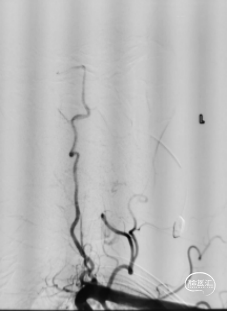

2. 左颈内动脉:(图2)

图2